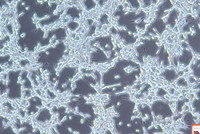

產品名稱 6-10b 鼻咽癌細胞株

組織來源 鼻咽癌

生長特性 貼壁生長

2.收到細胞先不開瓶蓋,瓶身擦拭酒精后放在培養箱靜置2-4小時(視細胞密度而定)穩定細胞狀態。接著在倒置顯微鏡下觀察細胞生長情況,并對細胞進行不同倍數拍照(建議收細胞時就整體外觀拍一張照片,觀察培養基的顏色和是否有漏液情況,隨后在顯微鏡下拍下細胞狀態,100*,200*各一張),觀察記錄細胞在運輸過程中是否有污染情況。作為我方進行銷售依據。